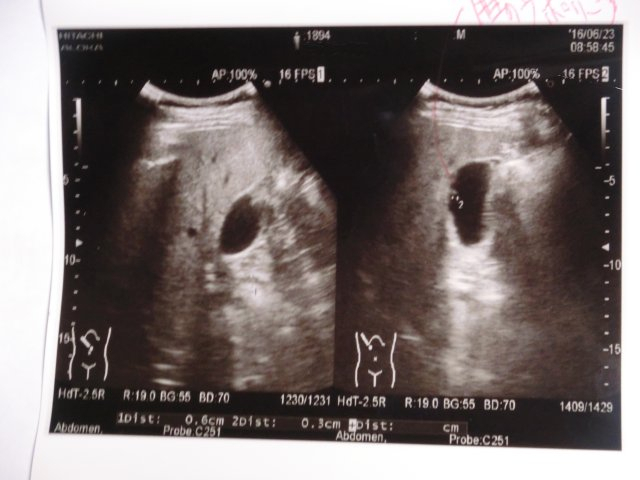

最初は超音波エコー検査

Cimg0189 左側の画像:腎嚢胞だって。

右側の画像:脂肪肝だって。

「腎嚢胞とは、腎臓にできる球状の袋のことで、中に液体を貯留しています。腎嚢胞では、悪性腫瘍 を伴ったり、また腎嚢胞が多発することで腎機能が悪化するタイプがあります。腎嚢胞の原因はよくわかっておらず、年齢とともに多くの人に発生し、エコー検 査やCT検査の際に偶然に発見されます。手術で腎嚢胞を切除し電気メスで焼く腎嚢胞開窓術という治療を行います。」

だって。

脂肪肝は中期だって。治療は食事療法しかないって。